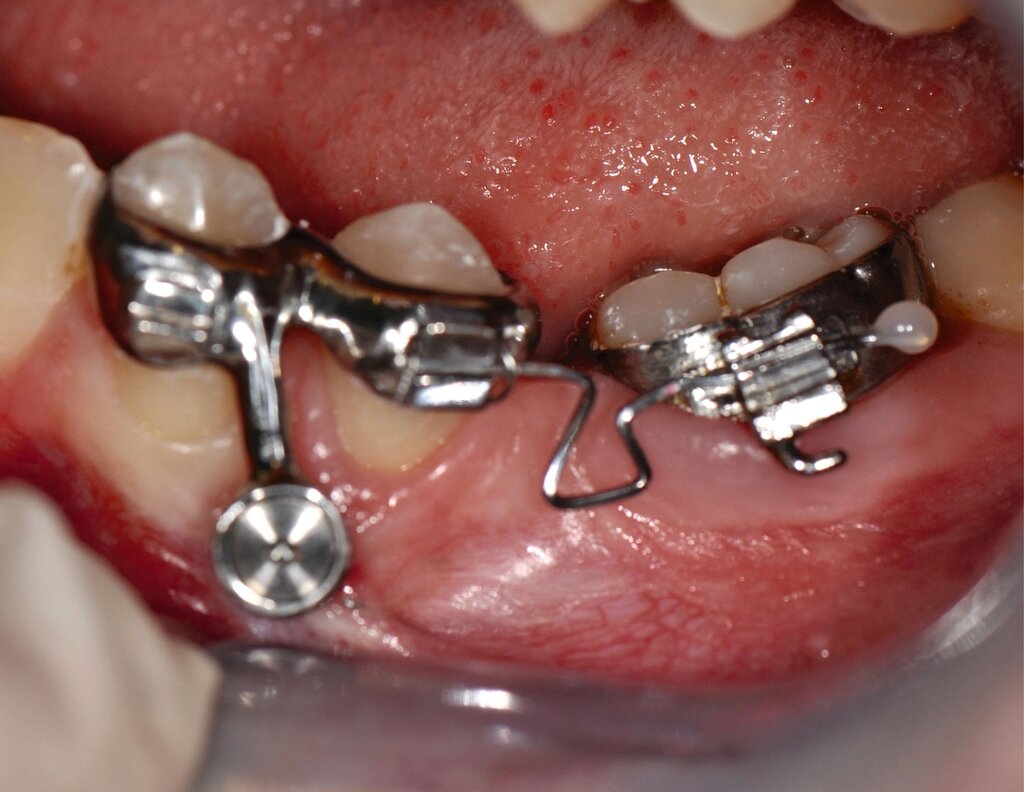

Als Alternative zu Alignern können auch Brackets mittlerweile im 3-D-Druckverfahren hergestellt werden [Sha et al., 2018; Sha et al., 2019; Bauer et al., 2023] (Abbildungen 2a und 2b). Neben der Nutzung des Angebots kommerzieller Anbieter (beispielsweise Lightforce Company) besteht dabei die Möglichkeit der Herstellung im praxisinternen 3-D-Drucker. Zum Einsatz eignen sich unter anderem Keramik-gefüllte 3-D-Druckkunststoffe der Biokompatibilitätsklasse IIa, die für einen langfristigen intraoralen Einsatz zertifiziert sind (zum Beispiel Permanent Crown Resin, Formlabs) [Papageorgiou et al., 2022; Bauer et al., 2023; Hodecker et al., 2023; Panayi, 2023].

Die Vorteile bestehen vordergründig in einem individualisierten Design, das die jeweiligen Therapieanforderungen berücksichtigt. Bisherige Forschungsarbeiten zeigen eine mit konventionellen Metallbrackets vergleichbare Präzision [Bauer et al., 2023], so dass eine korrekte Übertragung kieferorthopädischer Kräfte gewährleistet ist. Der Haftverbund zeigt sich gegenüber konventionellen Metallbrackets noch etwas schwächer [Hodecker et al., 2023]. Durch weitere Entwicklungen im Bereich der Bracketbasis dürfte diese Limitation jedoch adressiert werden können.

Auch die Herstellung zusätzlicher Elemente, wie beispielsweise Transpalatinalbögen aus Keramik-gefüllten 3-D-Druckkunststoffen, ist möglich (Abbildung 2c) [Thurzo et al., 2022], muss jedoch in großangelegten Studien noch auf eine ausreichende klinische Suffizienz untersucht werden. Weiter bieten 3-D-gedruckte Transferguides die Möglichkeit des „Indirekten Klebens“ [Deahl et al., 2007; Bozelli et al., 2013; Li et al., 2019; Sabbagh et al., 2022], wobei die Bracketpositionierung bereits vor dem Einsatz digital festgelegt und schließlich durch den Transferguide intraoral übertragen wird (Abbildung 2d). Neben einer verkürzten Stuhlzeit erlaubt dieses Verfahren eine besonders hohe Genauigkeit der Bracketpositionierung.